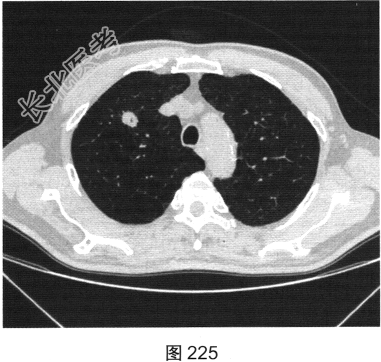

- [材料题] 患者女性,70岁。因“咳嗽、痰中带血3个月余”就诊。听诊无异常发现。胸部正侧位片发现右肺上叶类圆形小结节。

- 简答题2、患者行胸部CT检查,如图225、图226所示。请问该患者CT图像可见什么阳性表现?